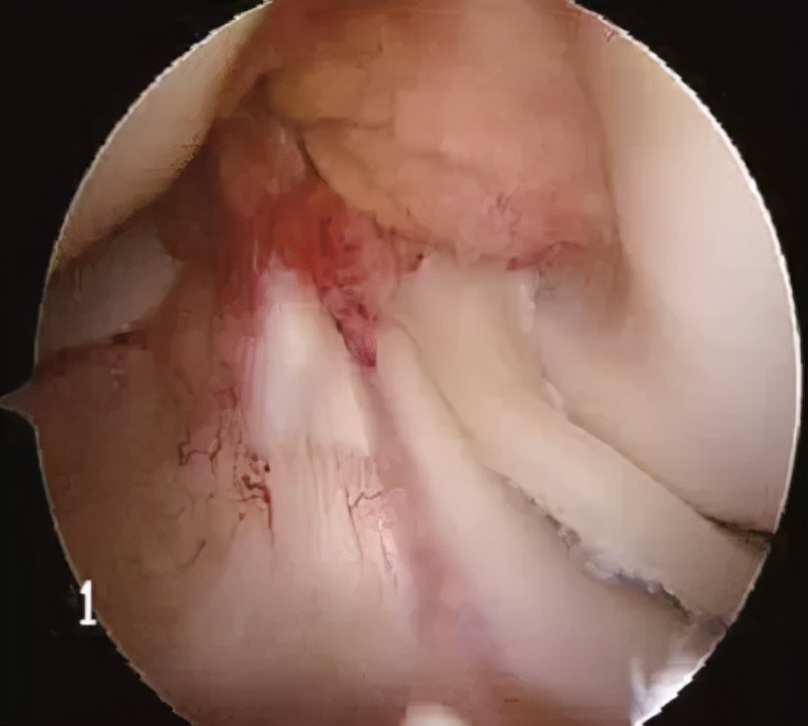

当进入到关节腔并清理周围增生的滑膜组织后,可以清晰地见到破损的半月板,半月板的损伤类型有多种( 不一定要“换膝盖”!关节镜微创手术,小切口,解决膝骨性关节炎! ),但处理原则是①去除不稳定的撕裂瓣;②切除缘修整成圆弧状;③尽可能保留半月板环的完整和宽度,对于保留功能具有重要意义;④防止损伤周围软骨。